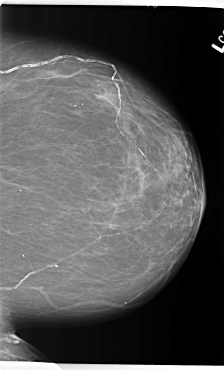

B_3141_1.LEFT_MLO

B_3141_1.LEFT_CC

LEFT_MLO LINES 5888 PIXELS_PER_LINE 3840 BITS_PER_PIXEL 12 RESOLUTION 50 NON_OVERLAY

LEFT_CC LINES 5912 PIXELS_PER_LINE 3584 BITS_PER_PIXEL 12 RESOLUTION 50 NON_OVERLAY